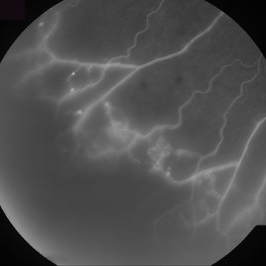

Ischemic BRVO

Aug 23 2012 by Gerardo Garcia-Aguirre, MD

Fluorescein angiogram of the inferotemporal periphery showing wide areas of capillary nonperfusion.

Photographer: Noemí Hernández, Asociación para Evitar la Ceguera en México

Condition/keywords: branch retinal vein occlusion (BRVO), capillary nonperfusion